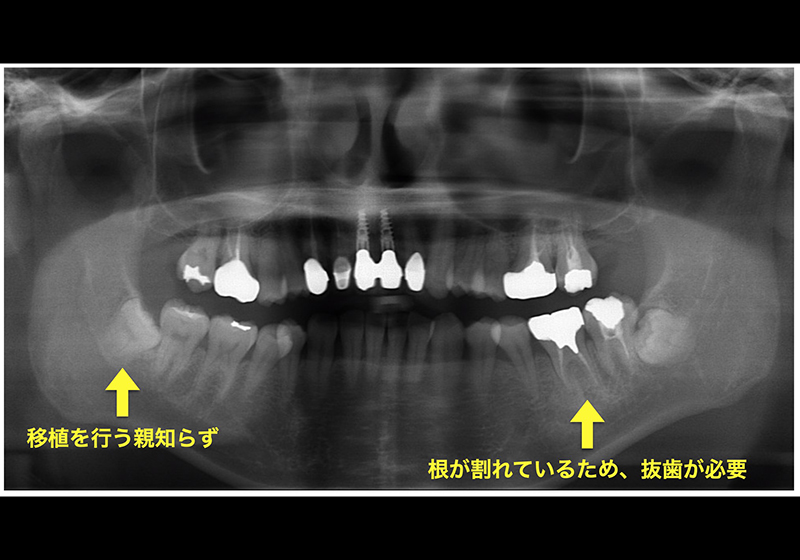

【①移植前レントゲン写真】

親知らず

【③抜歯した歯の根には大きな亀裂があった】